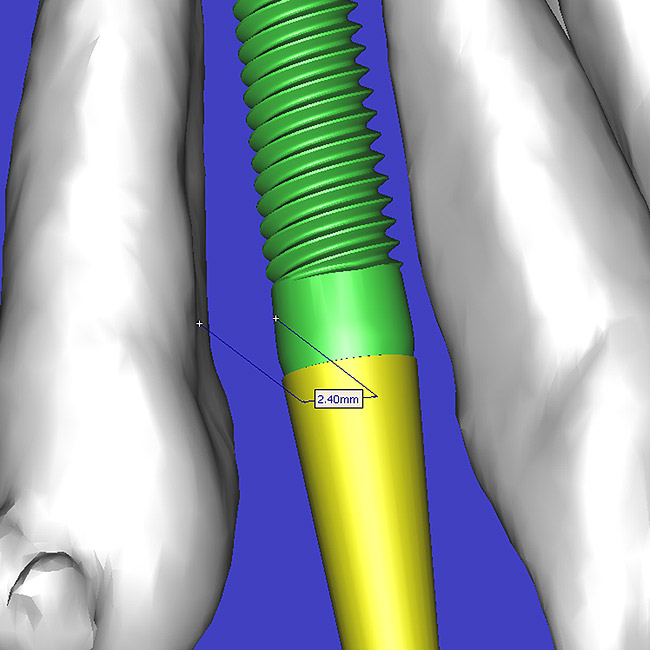

Using different masking (segmentation) and threshold Hounsfield unit values, several new 3D bone volumes can be created which offer invaluable information. To help determine the final position of each implant a new bone model was created with a Hounsfield unit value of 1480, which eliminated all but the densest objects included in the scan data. (Results may vary depending on the CBCT machine used.) The inner and outer layers of bone were removed, leaving the underlying enamel and root structure of the teeth (Figure 8A). After the bone had been stripped away, the root inclinations were examined closely. The most striking findings confirmed the rotated position of the right central, while revealing the slight mesial dilaceration of the root apex, which converged on the space needed for the path of the potential implant (Figure 8B). The schematic shapes of the proposed implants were visualized for the right and left lateral spaces in different rotations of the 3D maxillary arch. It was at this point that a determination was made as to the appropriate implant shape and type that would fit the available space while avoiding encroachment on adjacent tooth roots. A tapered design implant (Tapered Screw-Vent®, Zimmer Dental, www.zimmerdental.com) was chosen from the large virtual library. With the SIMPlant software, the virtual library contains data from dozens of implant manufacturers and realistic.computer-aided design representations as seen in Figure 9A through the translucent bone. The position of the left implant can be visualized with adequate mesial-distal distance between adjacent tooth roots (Figure 9B) and a more delicate placement (Figure 9C).

Figure 9a  Virtual implants were placed to determine the appropriate shape and type for the available space, in this case a tapered design allowed for adequate mesial-distal distance between adjacent roots.

Figure 9a

Figure 9b  Virtual implants were placed to determine the appropriate shape and type for the available space, in this case a tapered design allowed for adequate mesial-distal distance between adjacent roots.

Figure 9b

Figure 9c  Virtual implants were placed to determine the appropriate shape and type for the available space, in this case a tapered design allowed for adequate mesial-distal distance between adjacent roots.

Figure 9c